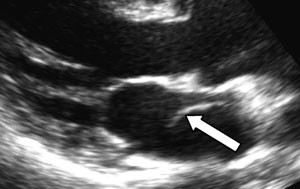

I tillegg til utredning med tradisjonelle ekkokardiografiske metoder ble pasienten også utredet med transtorakal tredimensjonal ekkokardiografi (fig 4), siden det nylig er rapportert at denne metoden kan erstatte transøsofageal ekkokardiografi i slike tilfeller.

Transtorakal tredimensjonal ekkokardiografi (3DE) har foreløpig liten utbredelse i klinisk sammenheng. Den seneste utviklingen innen transduserteknologi med muligheter for opptak i sanntid har forenklet og forbedret avbildningsprosessen betydelig (4). En av fordelene med 3DE-undersøkelse sammenliknet med transøsofageal ekkokardiografi er mindre ubehag for pasienten. I tillegg vil det gi en bedre kartlegging av de anatomiske strukturene, noe som er viktig dersom det blir nødvendig med kirurgisk behandling. Det er nemlig en betydelig utfordring å danne seg et godt tredimensjonalt bilde av strukturer inne i kroppen ut fra todimensjonale bilder. Nytten av tredimensjonale fremstillinger er naturligvis betinget av god bildekvalitet. Fra et apikalt vindu vil bildekvaliteten for strukturer i atriet begrenses av stor avstand fra lydhodet (proben). Fra et parasternalt vindu er god fremstilling av atriestrukturer, som en slik membran, også avhengig av en gunstig vinkel mellom lydbølgene og membranen. Hos denne pasienten var det parasternale vinduet best egnet til å fremstille membranen.